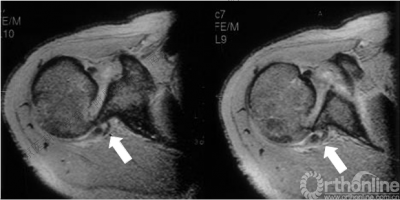

3.肩关节MRI

了解肩胛盂、肩袖及周围软性结构损伤情况。

盂肱下韧带肱骨侧止点撕裂

3.反Hill-Sachs损伤合并反Bankart损伤被Moroder命名为“双极损伤”。

4.δ角是发生肱骨头后脱位所需的肩关节内旋角度,在双极损伤中δ角减小,所以在双极损伤中,即使较轻的反Hill-Sachs损伤也需要修复。